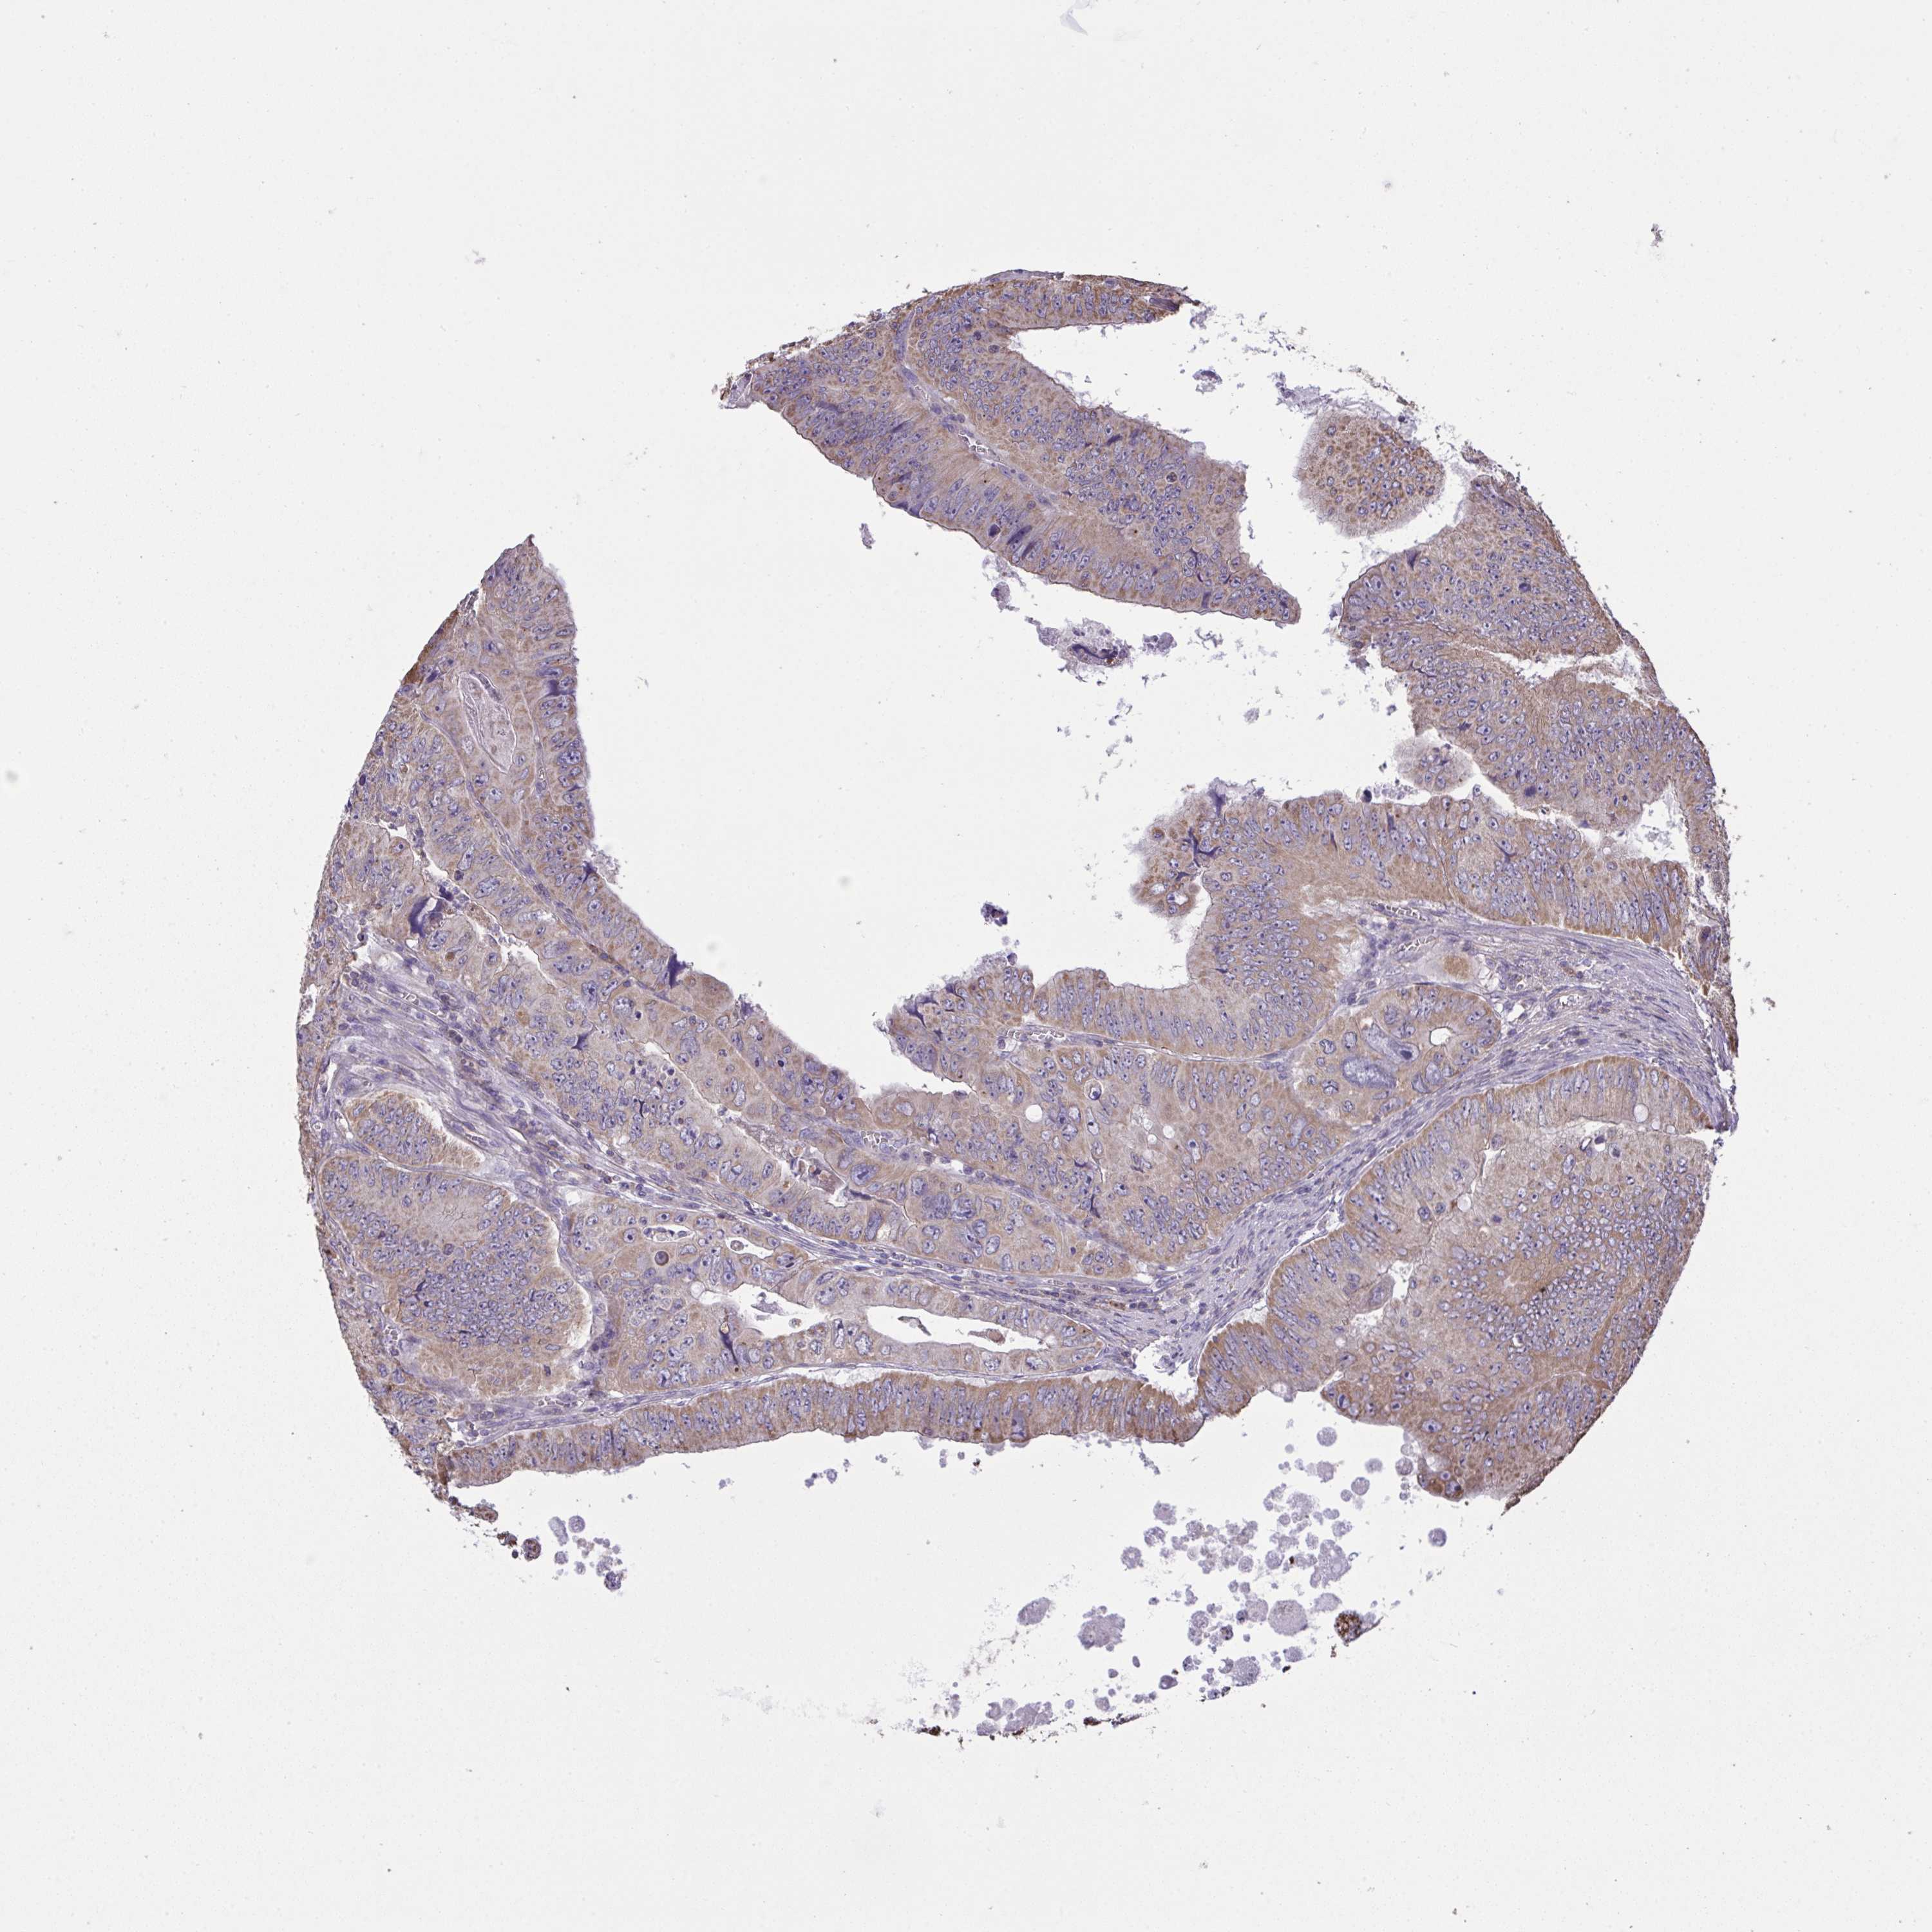

CANCER COLORECTAL CANCER Show tissue menu

Colorectal cancer

Human cancer